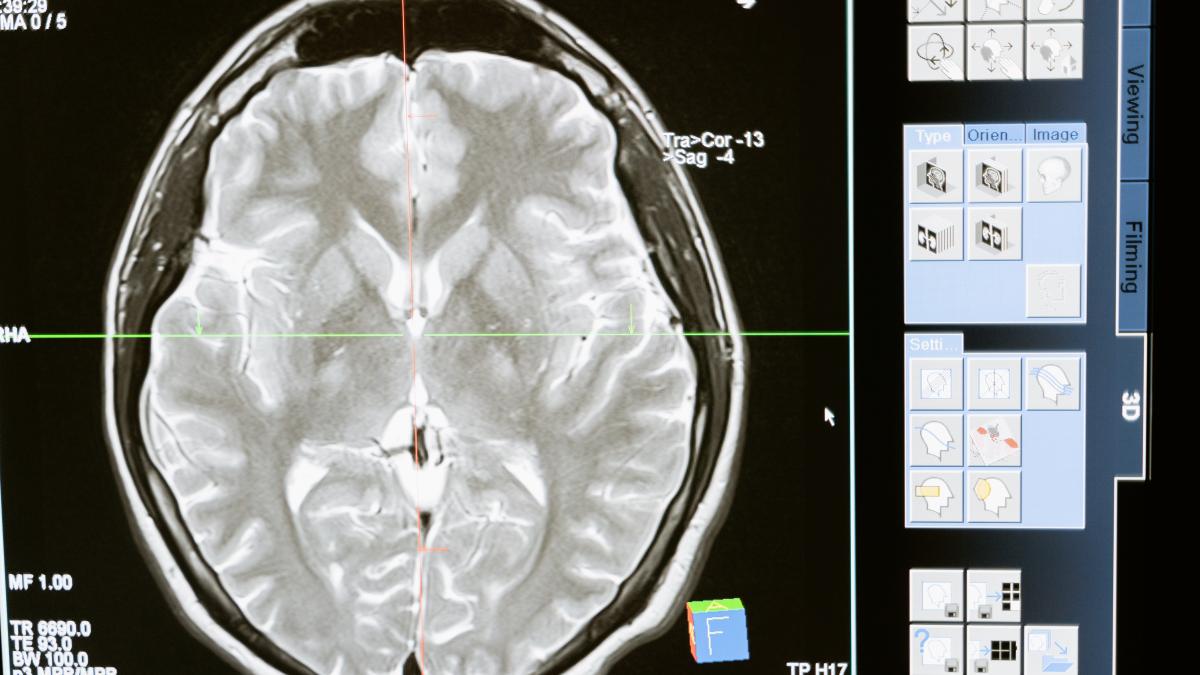

A fost identificat un ”circuitul cerebral” care oprește dependența de fumat

Renunțarea la fumat peste noapte este visul multora, dar nu este întotdeauna fezabil, împărțit între dorința de a reuși și dorința bruscă de a aprinde o țigară.

Alături de produse de înlocuire pe bază de nicotină sau alte medicamente și metode cu eficacitate dovedită, va fi posibil să ne gândim la  un anumit circuit cerebral care pare să fie implicat în stingerea dependențelor. Știrea este un studiu publicat recent în revista Nature Medicine, condus de cercetători de la Universitatea finlandeză din Turku, Centrul Medical Beth Israel Deaconess din Boston și Programul de cercetare intern al Institutului Național de Abuz de Substanțe din Baltimore, potrivit Veronesi.

Tratamentele bazate pe leziuni mici efectuate chirurgical și stimularea creierului sunt deja identificate ca opțiuni terapeutice promițătoare pentru stingerea dependenței de substanțe. Până acum însă, absența unei ținte definite către care să se îndrepte aceste terapii a limitat foarte mult eficacitatea acestora. Leziunile cauzate de traume pot fi utile în identificarea zonelor creierului implicate în mecanismele care stau la baza dependenței. De fapt, în circumstanțe rare, unii pacienți cu AVC au experimentat dispariția dependențelor, traducându-se astfel într-un beneficiu terapeutic pentru pacient.

Pentru a încerca să identifice circuitele creierului implicate în stoparea fumatului și a altor dependențe, cercetătorii au analizat scanări ale creierului a 129 de dependenți de tutun, realizate ca urmare a unor leziuni cerebrale localizate.

La cei 34 de pacienți la care a avut loc remiterea completă a dependenței, leziunile au fost toate atribuibile aceleiași rețele cerebrale, legate și de dependența de alte substanțe, cum ar fi alcoolul.

În prezent suntem încă departe și vor fi necesare cercetări suplimentare, dar circuitul identificat ar putea deveni, în viitor, o țintă terapeutică pentru noi tratamente împotriva dependenței de fumat și alte substanțe.